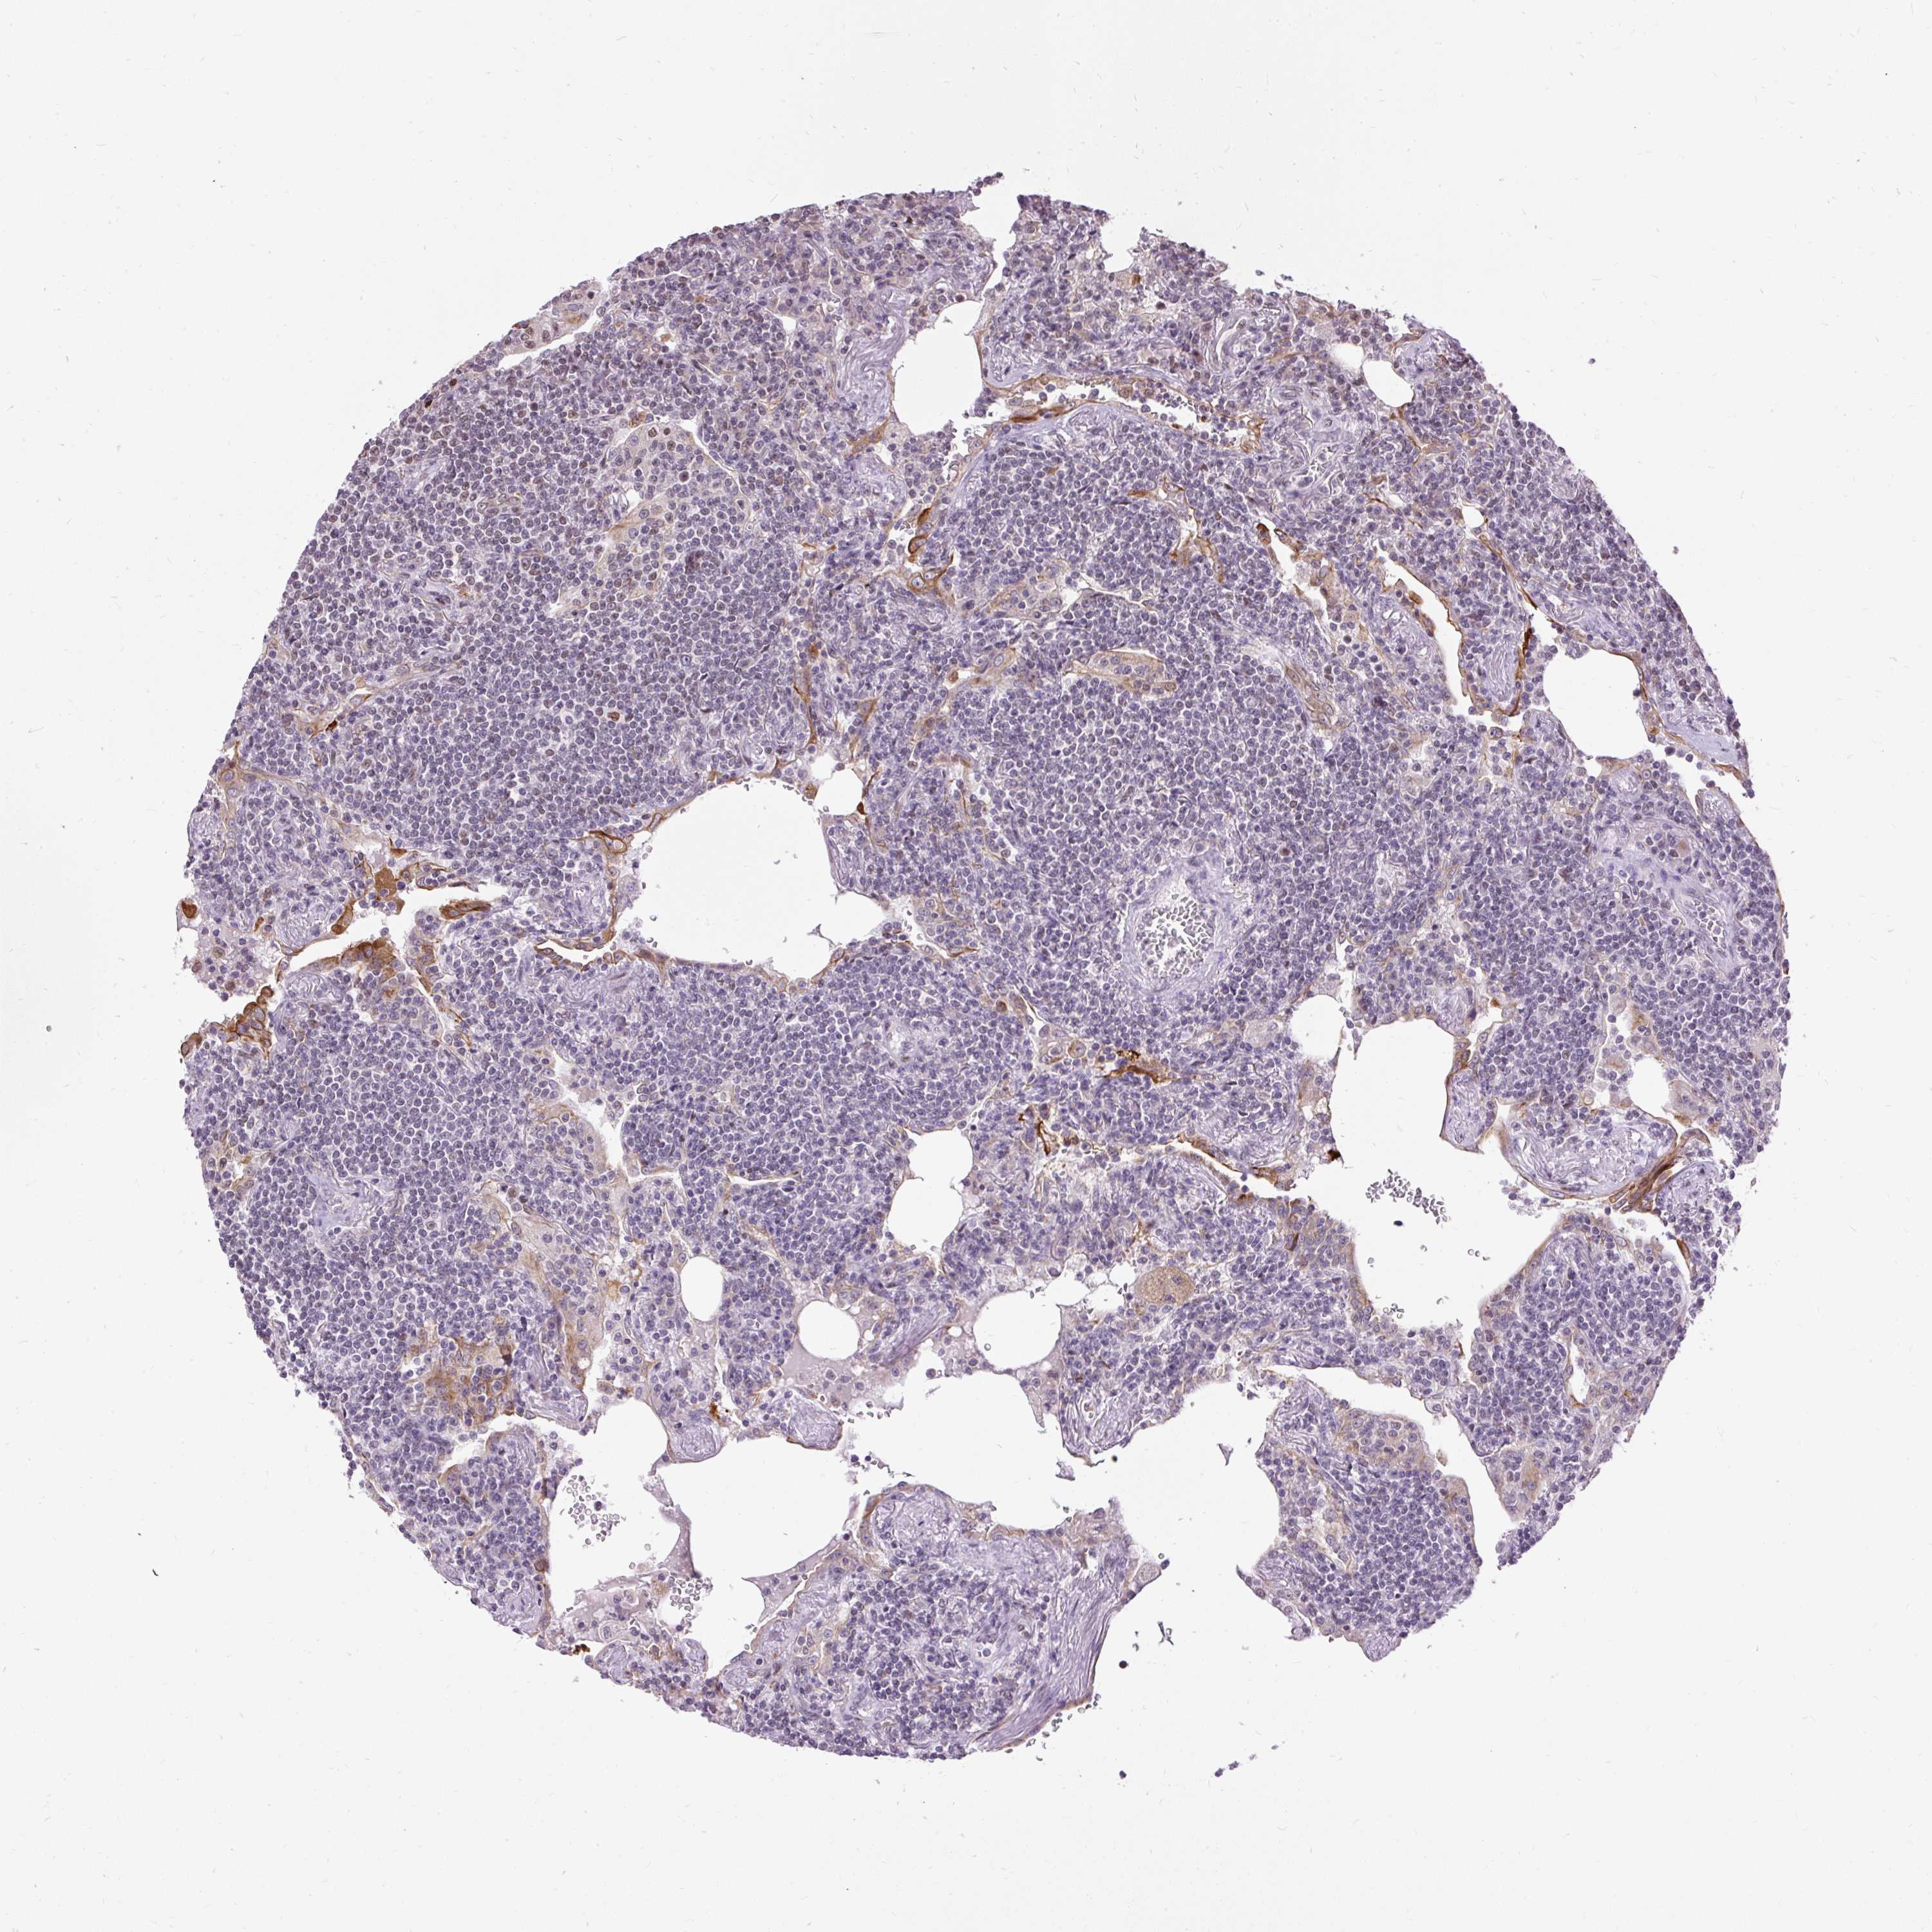

CANCER LYMPHOMA Show tissue menu

LYMPHOMA - Protein expressioni

A mouse-over function shows sample information and annotation data. Click on an image to view it in a full screen mode. Samples can be filtered based on level of antibody staining by selecting one or several of the following categories: high, medium, low and not detected. The assay and annotation is described here.

Antibody stainingi

Antibody staining in the annotated cell types in the current human tissue is reported as not detected, low, medium, or high, based on conventional immunohistochemistry profiling in selected tissues. This score is based on the combination of the staining intensity and fraction of stained cells.

Each image is clickable and will lead to virtual microscopy that enables deeper exploration of all samples and also displays staining intensity scores, fraction scores and subcellular localization as well as patient and tissue information for each sample.

Antibody HPA055779

Staining

High

Medium

Low

Not detected

Intensity

Strong

Moderate

Weak

Negative

Quantity

>75%

75%-25%

<25%

None

Location

Nuclear

Cytoplasmic/membranous

Cytoplasmic/membranous,nuclear

Malignant lymphoma, non-Hodgkin's type, Low grade

Malignant lymphoma, non-Hodgkin's type, High grade

Hodgkin's disease, NOS